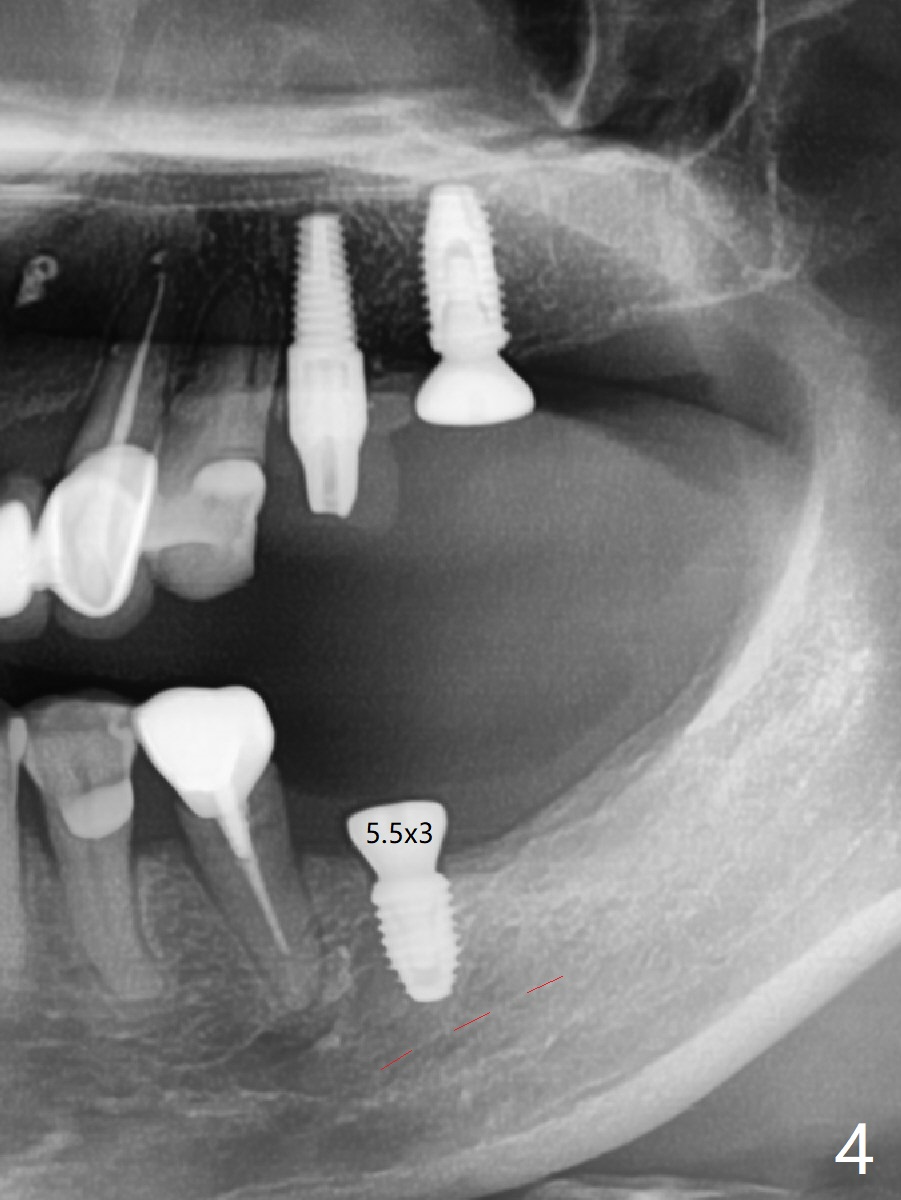

M

As a surgeon, I have never felt that my scalpel is as precise as media claims to be until guided surgery is introduced. The implants at #14 and 19 are placed as precisely as planned as well as painlessly and quickly (Fig.1-4). What else can we ask for? The gingiva around the healing abutment (5.5x3 mm) at #19 is erythematous (Fig.5). Later a longer healing abutment is used (Fig.6 (5.5x5 mm)). There is no bone loss 5 months or 7 months postop (Fig.6-9). The abutment screw is loose 3 months post cementation due to unfavorable crown/implant ratio (Fig.10); in fact the abutment is incompletely seated. Bicon implants will be in consideration to reduce screw loosening if implants are to be placed at #15 and 18. The abutment screw at #14 becomes loose 10 months post cementation; after retorque at #30 Ncm, the abutment is incompletely seated (Fig.11). It remains the same after use of 4.6 and 5.6 mm profile drills (Fig.12). A healing abutment is placed. When the patient returns, use planning kit and try to place a 5.2x5.5(2) cemented abutment. In fact it works (Fig.13). The crown at #19 is loose again 1 year 5 months post retightening. After removing crown/abutment, the mesial surface of the crown is heavily reduced. The crown/abutment is reseated to make sure that there is no proximal contact between the neighboring teeth (Fig.14 arrow). Because of tilt of the PA, it is difficult to tell the tightness of the contact between the implant and abutment, but the apical space is significantly reduced (*, as compared to Fig.10). Pick up impression is taken for porcelain addition occlusomesially. Two months later the patient returns for crown recementation. When the abutment is reseated with the repaired crown, the seating is incomplete (Fig.15). The abutment is completely seated when it is turned free hand with the flat surface of the abutment faces distal (Fig.16 D). The screw is torqued 20 Ncm before reimpression.